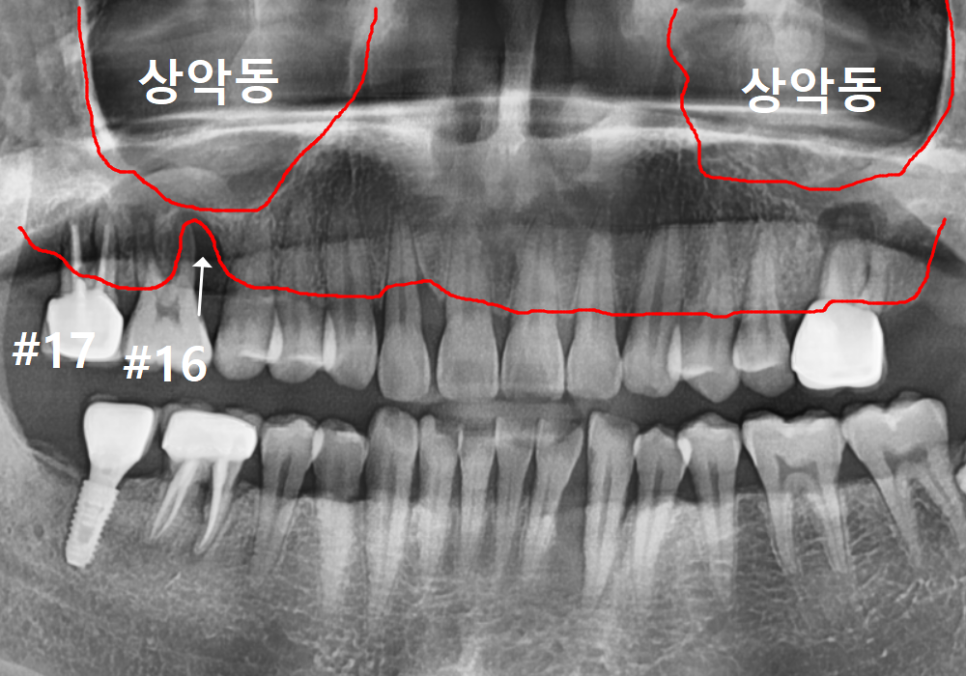

먼저 전체적인 상태를 보기 위해

파노라마 사진을 찍어보았습니다.

보시면 오른쪽 위 어금니(#16)는

뼈 흡수가 한눈에 봐도

심각하게 진행된 모습입니다.

그런데 그 뒤에 있는 치아인 #17은

앞에 치아에 비해 뼈가 크게 녹아 보이지 않으시죠?